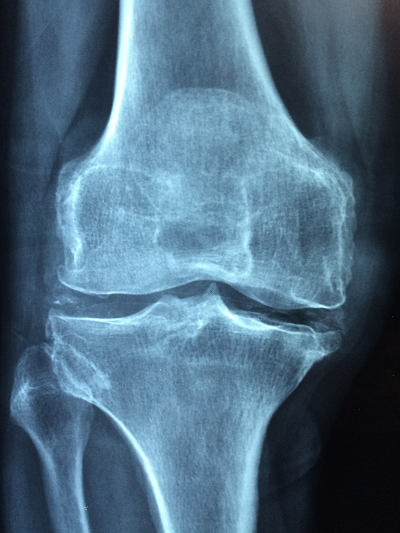

- 골절 및 뼈 약화: 골다공증의 발견은 특히 고관절, 척추, 손목 골절을 통해 우리에게 존재감을 나타내는 경우가 많으며 이는 뼈 강도가 저하되었음을 나타냅니다.